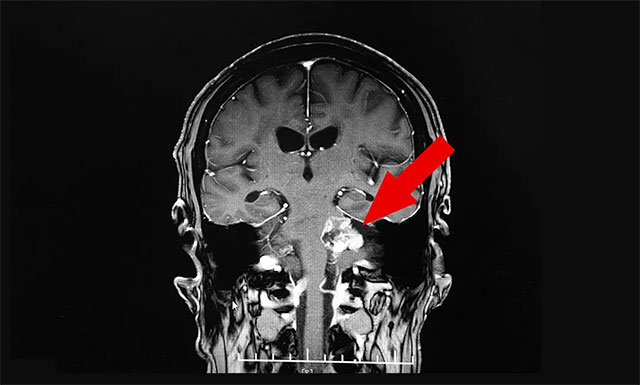

“因为老伴肢体功能恢复还不错,我们打算让他回家休养,而三个多月前老伴在外院和来蓝十字时做的都是头部CT检查,检查结果除了脑梗病症未见明确其他异常。为了让老伴放心出院,进一步了解其脑部情况,在周主任的建议下他进行了头部MRI检查,在查看影像结果时,细心的周主任却意外发现老伴左侧桥小脑角区有病灶,大小约为2.5cm×3.3cm,同时周主任还告诉我们,从影像资料上看老伴左侧听神经干增粗,很可能是听神经瘤”,听到此,管女士如五雷轰顶般顿时懵了。

随后,周主任仔细询问了患者的听力情况,据王先生反映,其听力近两年确实有所下降,但想着可能是自己年龄大的缘故,就没太在意。经过周主任细心检查,患者两侧听力都有所下降,但其左侧听力下降得更为严重。

▲ 细心的周主任发现了患者的新病症——“听神经瘤”

“周主任很专业又认真负责”,管女士对此说道:“为了能确诊,周主任还特邀医院神经外科6A病区主任侯增欣进行会诊,根据老伴的头部核磁共振检查结果,并结合他已出现的症状,最终老伴确诊为听神经瘤。而对于治疗,周主任和侯主任一致认为,由于老伴年龄较大,又身患多种疾病,如果手术,风险会比较大,建议我们放射治疗。”

当听到周君主任说听神经瘤是颅内一种良性肿瘤,可以治疗时,管女士和儿子才终于松了一口气,对于他们来讲,老伴遭受的已经很多了,真不愿意他再遭受任何疾病的折磨了。

“在蓝十字治疗我们很放心,对于听神经瘤的后续治疗,我们还会选择蓝十字。蓝十字医生医德双馨,护士更是爱心无限,不仅让老伴重新站了起来,还接二连三地发现了他的新病症,尤其是听神经瘤,幸好发现及时,如果肿瘤继续增大,压迫同侧的面神经和三叉神经,不仅会出现面肌抽搐,严重时还会导致面瘫等严重并发症……”,管女士感激道。